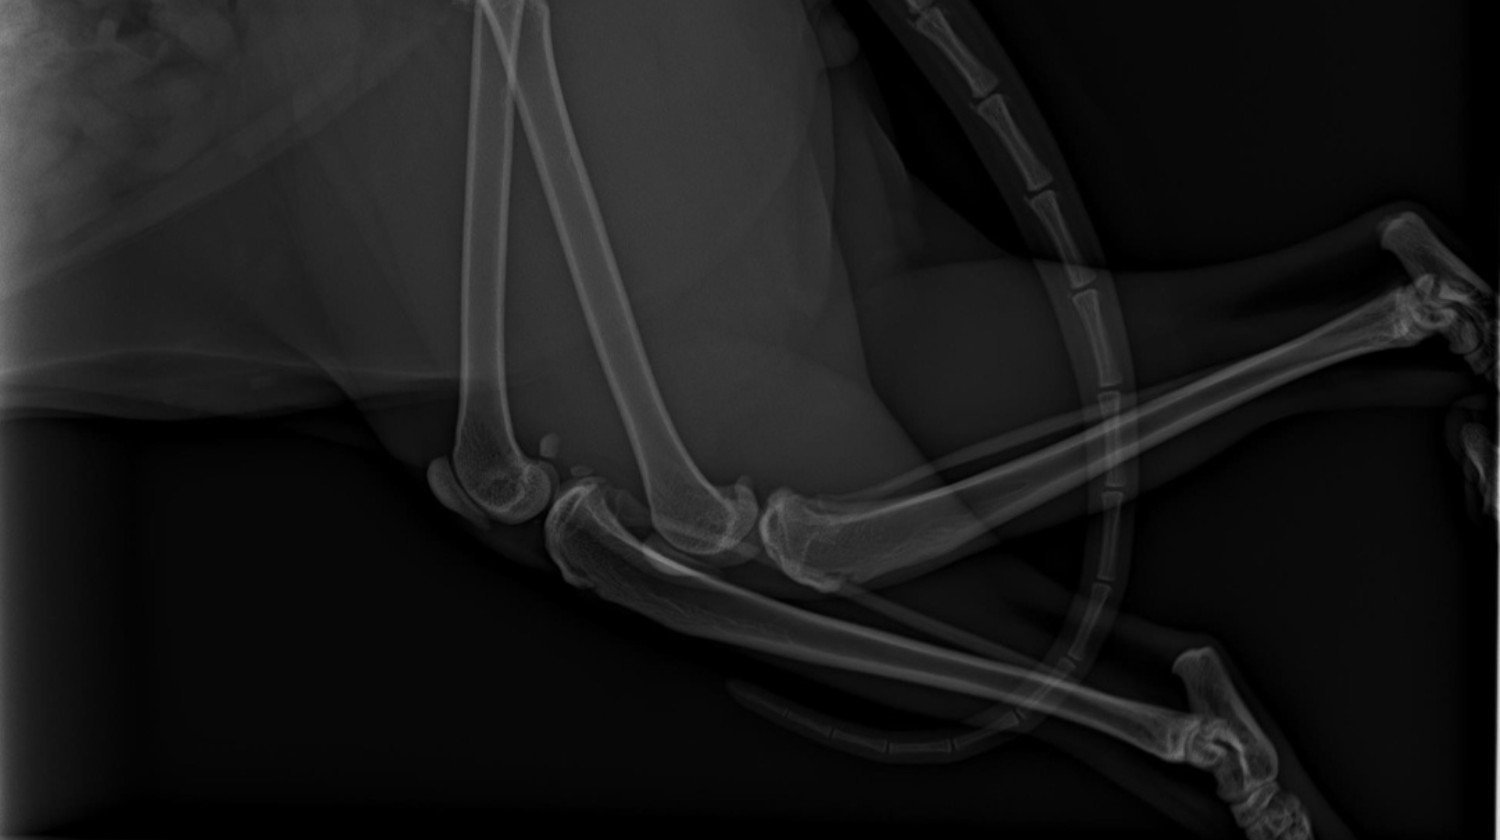

Notre famille vient de vivre une tragédie déchirante : notre chat bien-aimé a été renversé par une voiture. Sa patte est gravement cassée, elle souffre énormément et les vétérinaires disent que seule une intervention chirurgicale immédiate et salvatrice peut lui donner une chance de survivre. Chaque minute d'attente diminue ses chances.

L'opération, le traitement médical intensif, les frais de déplacement et l'hébergement nécessaire à proximité de l'hôpital vétérinaire s'élèvent ensemble à 1660 euros - une somme que notre famille ne peut tout simplement pas se permettre en ce moment. Nous sommes dévastés parce que nous ne pouvons pas lui apporter l'aide dont elle a besoin de toute urgence.

Une immense tragédie est arrivée à notre famille : notre chat adoré a été renversé par une voiture. Dans l'accident, sa patte a été gravement cassée, il souffre énormément, et les vétérinaires disent que seule une chirurgie immédiate et salvatrice peut lui donner une chance de survie. Chaque minute d'attente diminue ses chances de survie.

L'opération, les soins intensifs, les frais de déplacement et l'hébergement à proximité de l'hôpital vétérinaire coûtent au total 1 660 euros, ce qui est hors de notre portée pour l'instant. Notre famille est dévastée car nous ne pouvons pas lui apporter l'aide financière qu'il mérite.